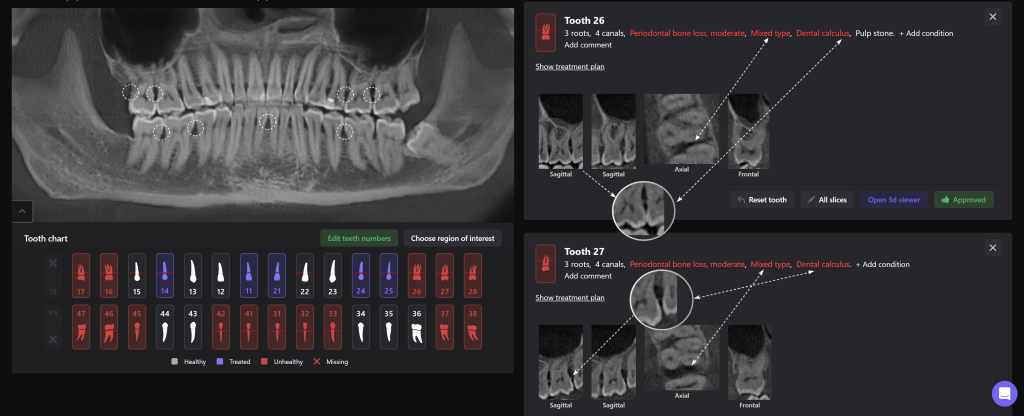

A complete diagnosis is the basis for a correct and timely treatment. In this periodontal case a patient complained of sore gums and bleeding, which had bothered her for several years.

With the help of Diagnocat STL reconstruction, the doctor can visualize changes in the level of bone relative to the roots of the teeth, which are hidden behind the gum.

A cross-sectional radiological report created by Diagnocat AI allows the clinician to detect a subgingival calculus and make an accurate prognosis of each tooth before starting any complex treatment, whilst taking into account all of the endodontic, periodontal and functional criteria.

Thanks to all the data gathered by Diagnocat, a plan was created which achieved a positive treatment result.